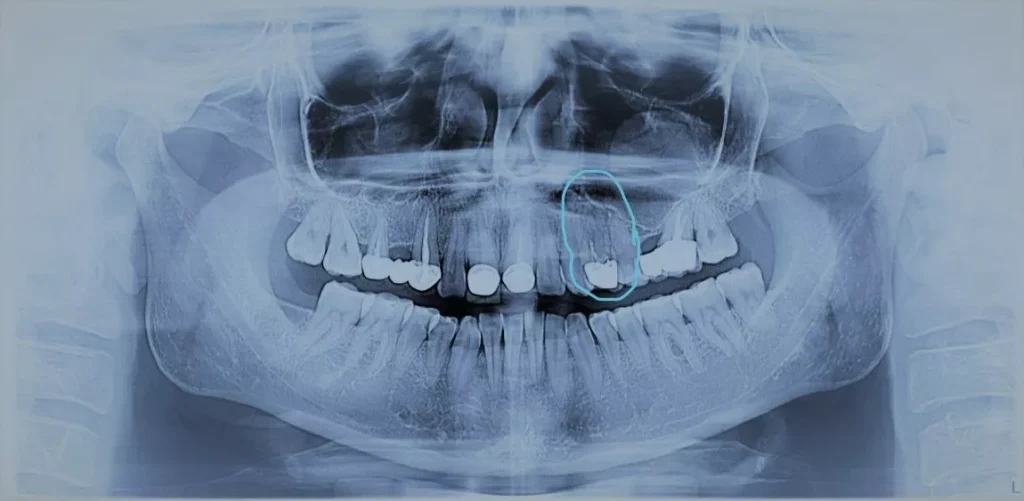

Radiografia dentară 2D este cea mai răspândită investigație radiologică folosită în stomatologie. La început, era utilizată doar pentru analiza unui singur dinte sau a unui grup restrâns, deoarece tratamentul se concentra pe zona dureroasă.

Odată cu evoluția tehnologiei, radiografia panoramică – ortopantomografia – a devenit accesibilă, oferind o imagine completă asupra danturii. Astfel, medicul poate susține științific deciziile de tratament și poate preveni apariția unor probleme.

Acest tip de imagine, chiar dacă oferă o suprapunere de structuri, permite identificarea unor afecțiuni precum:

• Localizarea și determinarea distanței față de structuri anatomice importante

• Aprecierea poziției leziunilor dentare

• Depistarea recidivelor de carie și a cariilor secundare

• Identificarea chisturilor, osteitelor, granuloamelor, parodontozei, infecțiilor și inflamațiilor